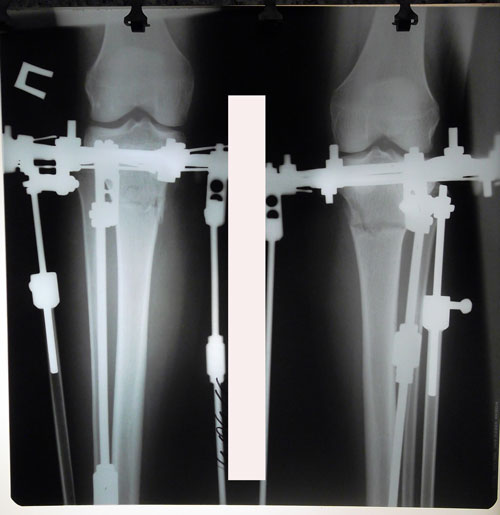

Исходник - 22 года.

Ротация справа под вопросом.

Дата операции 29.03.2016г.